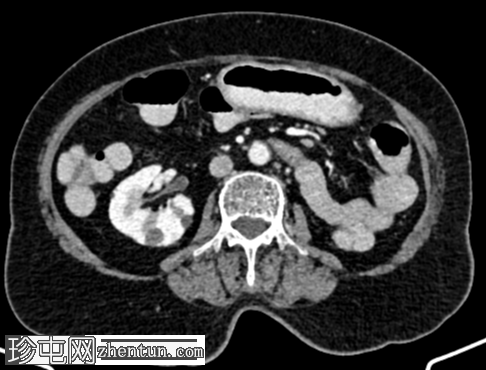

轴位

平扫

左肾及左肾动脉缺如。

左侧肾上腺呈垂直方向。

左侧盆壁可见一管状扩张(直径16.5 mm)的充满液体的结构,该结构在S1椎体水平突然向上变窄,然后继续向上延伸,形成轻度强化的纤维条索状结构,直至L5椎体上终板水平。扩张管状结构的尾端逐渐变细,可能终止于阴道穹窿左侧角。在管状结构的尾端可见数个微小的高密度灶,可能为下垂性病灶(其中一个大小为 3.3 mm,315 HU)——可能为结石或钙化。未见其他左侧输尿管样结构。未见左侧膀胱输尿管连接处。

右肾可见多个低密度、无强化的单纯性皮质囊肿和数个高密度、无强化的囊肿——Bosniak II 级。

肝脏 VI 段包膜下可见一个低密度、低强化的单纯性囊肿(大小为 34.4 x 33.6 x 31.1 mm)。

左侧髂总静脉延续为左侧髂外静脉。左侧髂内静脉未汇入左侧髂总静脉,而是汇入右侧髂内静脉,并在 S1 椎体水平跨越中线。

左肾发育不全,左肾动脉缺如,左侧肾上腺呈平卧位征。

左侧输尿管远端三分之一处呈盲端扩张,异位开口,可能位于阴道穹窿。